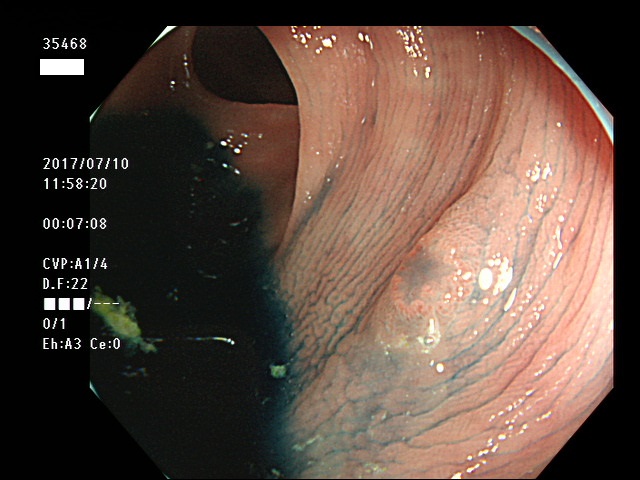

上記100名より抽出した平坦・陥凹型腺腫・SSAP(=癌化の危険が高いが見落としやすい病変)の内視鏡写真

35403 35404 35405 35409 35410 35412 35413 35414 35416 35417 35418 35419 35420 35421 35426 35429 35430 35433 35434 35435 35438 35439 35440 35444 35445 35447 35449 35450 35451 35452 35453 35454 35458 35460 35463 35464 35466 35468 35469 35470 35472 35473 35478 35479 35481 35483 35485 35489 35490 35491 35492 35493 35498 ・・・・・の54名